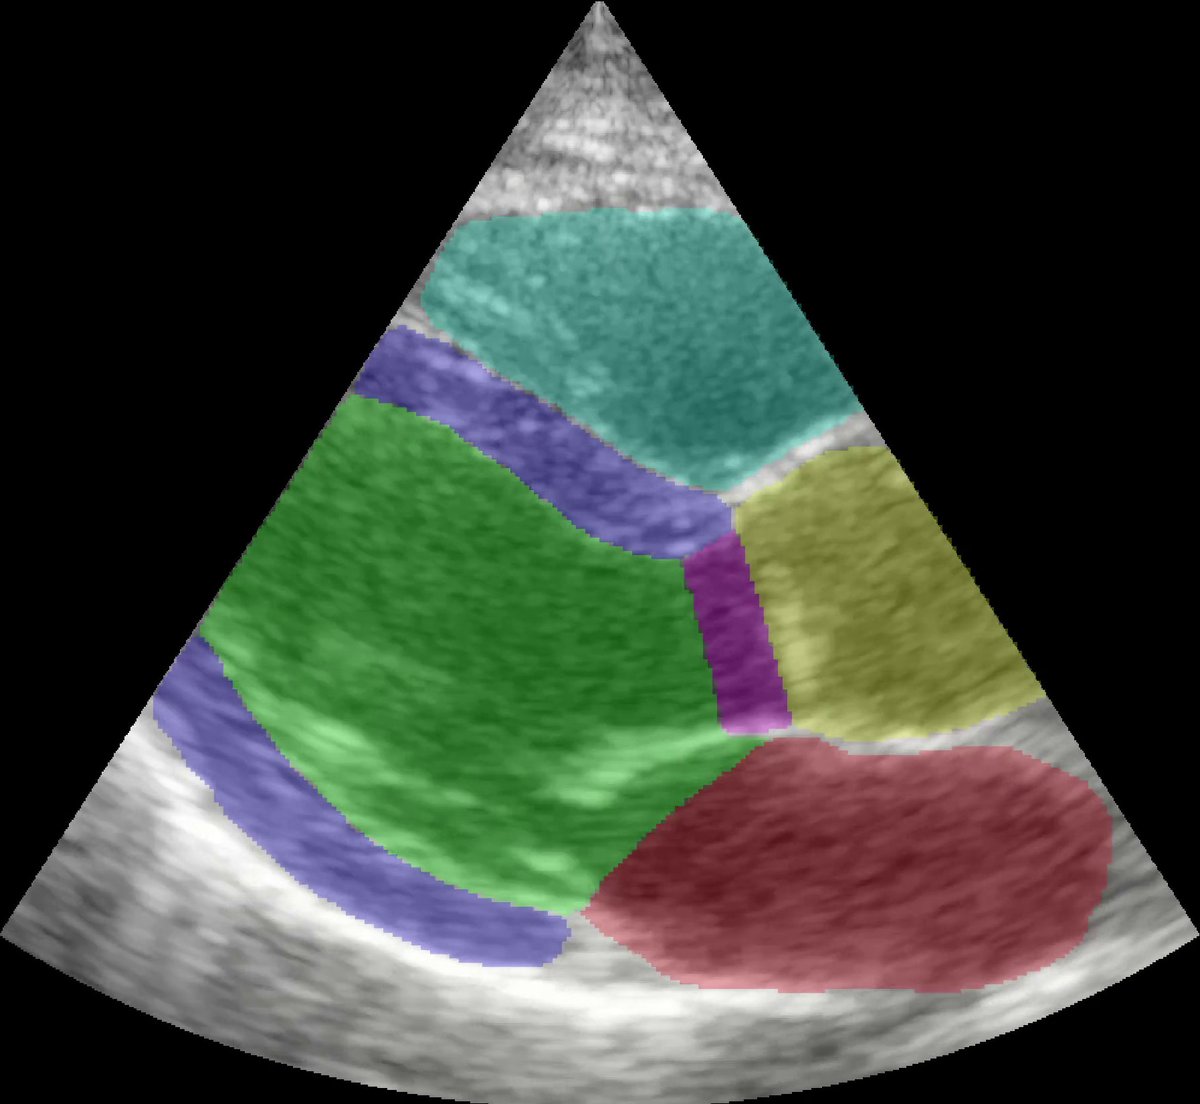

Our latest article on real-time ejection fraction and apical foreshortening detection using #deeplearning is out: eriksmistad.no/wp-content/upl… #openaccess #echocardiography #ultrasound #cardiac #ejectionfraction

Using #deeplearning and #AI we can perform fully automated measurements of left ventricular function by strain #echocardiography, with excellent correlation to the reference method. Read more in our latest article in #JACCIMG! sciencedirect.com/science/articl…